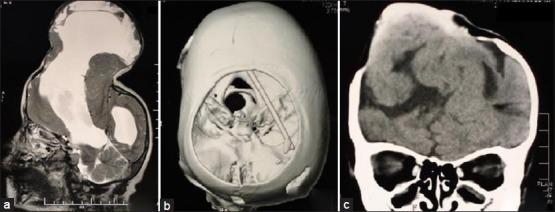

An encephalocele is a developmental disorder of neural tube closure, where as schizencephaly is a developmental disorder of neuronal migration. There are only few case reports suggesting association of schizencephaly with meningoencephalocele. We report a case of 6-year-old child who was brought by her parent with complaints of progressive swelling over her vertex since birth, left sided hemiparesis and intermittent generalized tonic clonic convulsion for last 3 years. Clinical examination, computed tomography (CT) and magnetic resonance imaging (MRI) of brain revealed a large calvarial defect with meningoencephalocele and associated schizencephaly. Initially, ventriculoperitoneal (VP) shunt was carried out, followed by successful repairing of the defect. This case is interesting for late presentation, management difficulties and associated anomalies "schizencephaly", which is a rare developmental disorder.

https://cdn.ncbi.nlm.nih.gov/pmc/blobs/57ed/4166835/829b3f8b5fc8/JPN-9-136-g001.jpg